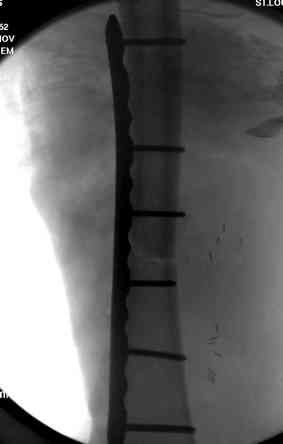

здесь случай с политравмой, перелом зафиксирован наружным фиксатором, после третьей irrigation&debridment фиксация бедра пластиной с последующей кожной пластикой.